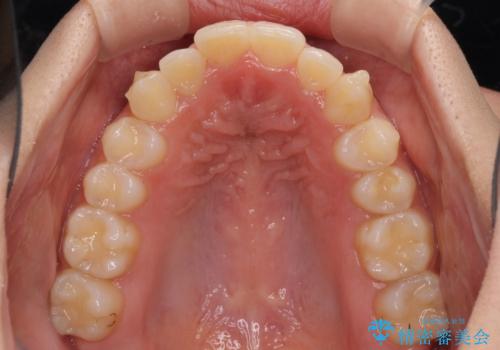

骨格的に左右にずれいている 前歯のデコボコをインビザラインで解消

- 前歯のデコボコと八重歯を気にして来院された患者様です。

叢生の程度は中等度であったため、IPR(歯と歯の間を削る)と歯列の側方拡大をメインに、インビザラインを用いて歯列を改善することとしました。